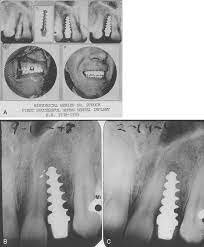

Alvin Strock inserta el primer implante de tornillo dental Vitallium

Per-Ingvar Branemark describe técnicas para la osteointegración de implantes dentales.